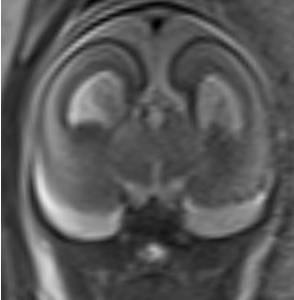

In the presented case, the patient's diagnosis of a tubulinopathy  (TUBB3), specifically involving the TUBB3 gene, is supported by both prenatal ultrasound and subsequent MRI findings. The ultrasound demonstrated and the MRI show callosal agenesis. Furthermore, the MRI shows a diffuse abnormality in sulcation/gyration, with shallow appearance of many large sulci. The sagittal images also show an atypical appearance of the brain stem, which appears "kinked". These findings are characteristic of tubulinopathies and highlight the pivotal role of TUBB3 in neuronal migration, commissural formation, and cortical folding.

Tubulinopathies constitute a complex group of neurological disorders characterized by specific structural brain anomalies, notably cerebellar hypoplasia (78%), dysmorphic basal ganglia (75%), and callosal dysgenesis (40%). These disorders highlight the critical role of tubulin proteins in axonal pathfinding and brain development, particularly evident in the severe phenotypes of fetal tubulinopathies. While postnatally the dysmorphic appearance of the basal ganglia constitutes a salient feature, this is difficult to identify prenatally.